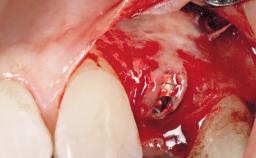

Immediate Placement of an Implant in a Maxillary Left Central Incisor Site

A 33-year-old female patient presented with an upper left central incisor that required extraction after a failed endodontic therapy. The tooth had been traumatized when the patient was a teenager and had undergone several endodontic treatments, including two apicectomy procedures. The patient was in good health and did not smoke. Clinical examination showed that the patient had a high lip line. In full smile, the gingival margins of the upper teeth were visible to the first molars. The gingival margins of central incisors 11 and 21 were only just showing. Examination of tooth 21 confirmed that the tooth was mobile and had hypererupted by 1 mm.

Placement Protocol | Immediate implant placement |

Socket Integrity | Damage to one or more bone walls |

Bone Volume | Damage to one or more socket walls |